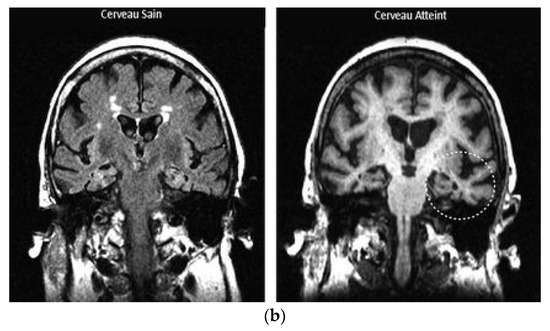

Intraoperative ultrasound (IOUS) has developed from a rudimentary adjunct into a versatile modality that now plays a crucial role in neurosurgery. Offering real-time, radiation-free and repeatable imaging at the surgical site, it provides distinct advantages over intraoperative magnetic resonance (MRI) and computed tomography [...] Read more.

Intraoperative ultrasound (IOUS) has developed from a rudimentary adjunct into a versatile modality that now plays a crucial role in neurosurgery. Offering real-time, radiation-free and repeatable imaging at the surgical site, it provides distinct advantages over intraoperative magnetic resonance (MRI) and computed tomography (CT) in terms of accessibility, workflow integration and cost. The clinical spectrum of IOUS is broad: in cranial surgery it enhances the extent of resection of gliomas and metastases, supports dissection in meningiomas and enables localization of MRI-negative pituitary adenomas; in spinal surgery, it guides resection of intradural and intramedullary tumors, assists in myelotomy planning and confirms decompression in degenerative conditions such as cervical myelopathy and ossification of the posterior longitudinal ligament. IOUS also offers unique insights into cerebrospinal fluid disorders, including arachnoid webs, cysts, syringomyelia and Chiari malformation, where it visualizes cord compression and CSF flow restoration. In trauma and oncological emergencies, it provides immediate confirmation of decompression, directly influencing surgical decisions. Recent innovations, including contrast-enhanced ultrasound, elastography, three-dimensional navigated systems and experimental integration with artificial intelligence and robotics, are extending its functional scope. Despite heterogeneity of evidence and operator dependence, IOUS is steadily transitioning from an adjunctive tool to a cornerstone of multimodal intraoperative imaging, bridging precision, accessibility and innovation in contemporary neurosurgical practice. Full article